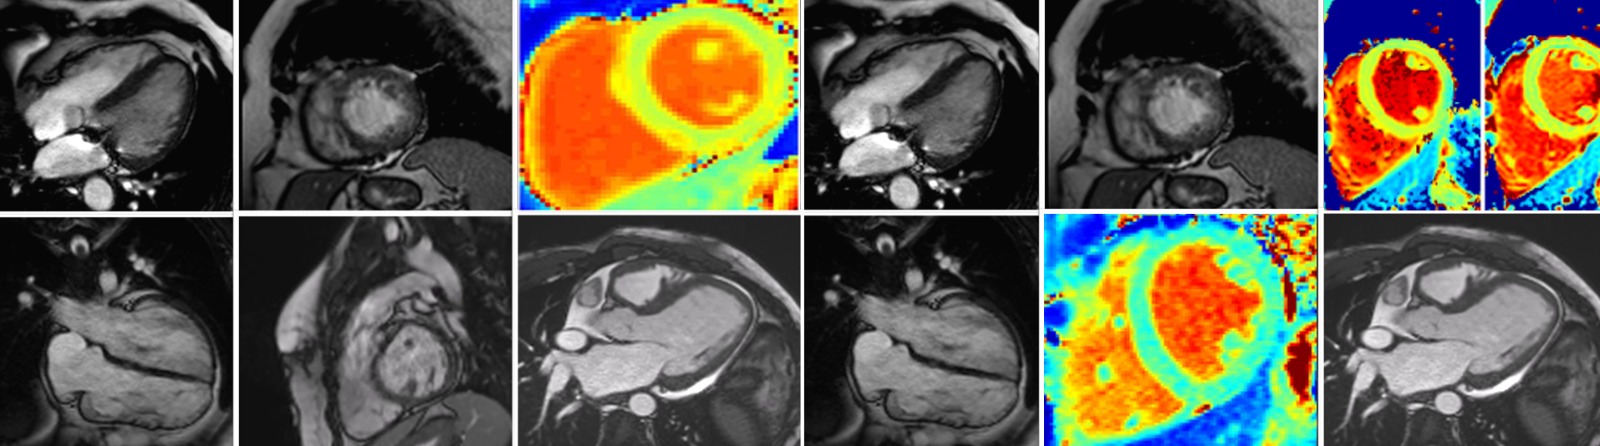

Rezonanța magnetică cardiovasculară (Cardio-RM) este cea mai avansată metodă imagistică de evaluare a funcției inimii. La Emerald, investigația este realizată de o echipă formată dintr-un medic radiolog cu experiență și un medic cardiolog specializat în RM cardiovasculară, în timpul acesteia fiind preluate peste 1500 de imagini de pe inimă, cu ajutorul unui aparat de ultimă generație, mai rapid, mai precis și mai silențios. Rezonanţa magnetică este o scanare nedureroasă și inofensivă, ce permite să privim în interiorul corpului fără utilizarea razelor X. Cu ajutorul unui magnet şi a undelor radio obţinem imagini detaliate, de foarte bună calitate cu privire la structura şi funcţia inimii.

Centrul Medical Emerald se află în acest proces de certificare europeană de peste 8 luni de zile, existând o listă foarte strictă de criterii, de la echipamentele tehnice și software folosite la acreditările echipei medicale, numărul de investigații realizate și chiar tipurile de secvențe utilizate, fiind obligatorii o înaltă calitate a examinărilor și acoperirea unei arii mari de patologii, incluzând patologii congenitale, cardiomiopatii, miocardită sau boală cardiacă ischemică.

Este indicată în cazul următoarelor patologii: Insuficiență cardiacă, Cardiomiopatie hipertrofică, Miocardită, Fibroză miocardică, Cardiomiopatie dilatativă, Displazie aritmogenă de ventricul drept, Bloc de ramură stângă, Extrasistole ventriculare, Aritmii ventriculare, Resincronizare cardiacă, CRT, Talasemie, Hemocromatoză, Amiloidoză, Boala Fabry, Regurgitare aortică, Insuficiență aortică. La Emerald se efectuează și rezonanță magnetică cardiacă de stres, o investigație nouă în Romania, dar foarte utilizată în celelalte țări europene, dedicată unor patologii speciale, cum ar fi: Boală cardiacă ischemică, Infarct miocardic acut, Cardiopatie ischemică, Angină pectorală, Stenturi coronariene, Bypass aorto-coronarian.